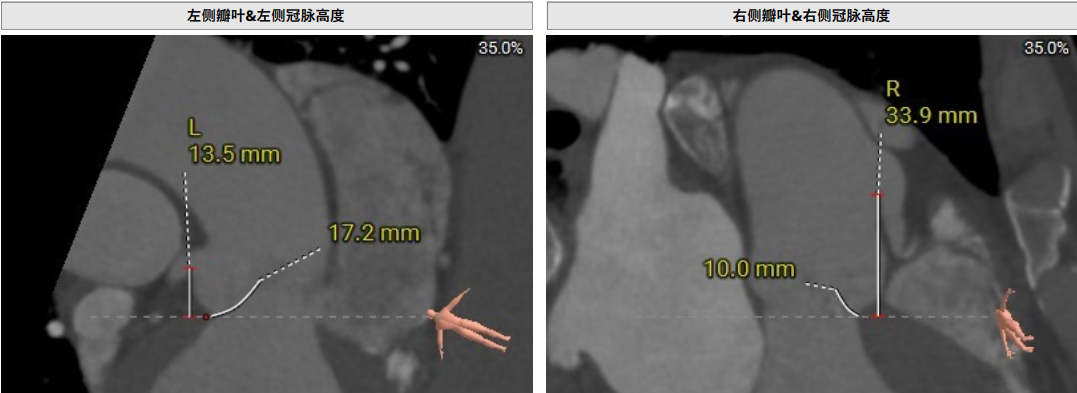

術前CT評估提示,患者主動脈瓣三葉瓣,瓣葉增厚,舒張期右冠瓣脫垂,右冠瓣瓣葉輕度鈣化,存在三個瓣竇,分布較均勻;主動脈瓣環周長折算直徑28.0mm;左心室流出道周長折算直徑29.5mm,無鈣化,無狹窄;STJ直徑35.3mm,升主動脈直徑41.8mm;雙側冠脈開口高度可LCA13.5mm ,瓣葉長17.2mm;RCA33.9mm,瓣葉長10.0mm;側左冠脈輕度鈣化;橫位心,左室主動脈夾角為135°;